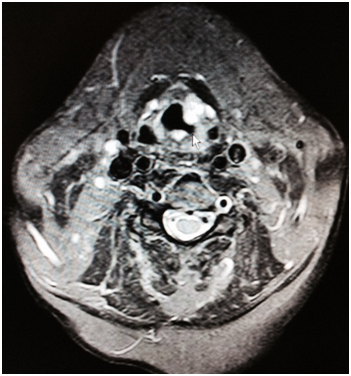

An 80-year-old Caucasian woman presented in our ENT department due to a progressive swelling on the left parotid gland during a period of two months. The physical examination showed a soft and mobile mass on the left parotid gland. The flexible fiber optic laryngoscopy showed a mass in the left laryngeal ventricle with intact laryngeal mucosa. The ultrasound of the salivary glands showed a multi - lobular tumor of both left and right parotid glands. The MRI scan showed a 1.2 x 1.1cm solid tumor in the left supraglottic region, without infiltration of adjacent tissues. In the parotid region was a 2.7 x 1.8cm solid mass in the left parotid gland as well as a 0.8 x 1.2cm solid mass in the inferior lobe of the left parotid gland (Figure 1&2). The patient was operated under general anesthesia. The larynx tumor was resected via transoral laser excision and the parotid tumor of the left side was resected via lateral parotidectomy. The histopathological examination showed a cystadenolymphoma that consist of an oncocytic epithelial cell component arranged in double layers, which develops cysts and papillary projections, and a variable amount of lymphoid tissue with germinal centers (Figure 3). An oversupply of lymphoid stroma with a characteristic formation of lymph follicles (Figure 4) was observed in all histological specimens with hematoxylin and eosin stain. There were no granulomas and no evidence of bacterial, fungal, or parasitic infection. The final diagnosis was a cystadenolymphoma in the morgagni sinus as well as multiple lesions in the parotid gland, compatible with a cystadenolymphoma. After consulting the patient, an ultrasound controlled fine needle aspiration of the tumor of the right parotid gland was performed. The histopathological examination showed a cystadenolymphoma of the right parotid gland.